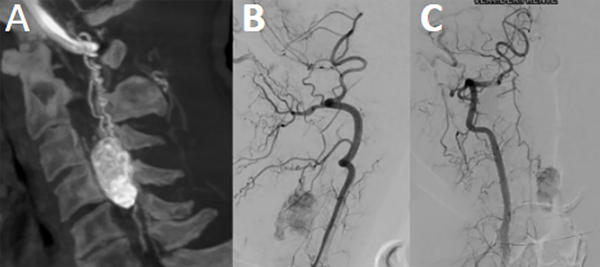

Fig 2. Caso 1. Angiografía cervical espinal evidenciando “blush” tumoral con aferencia primaria de arteria espinal posterior (A, B y C).

Fig 8. Caso 3. Angiografía espinal torácica: evidenciando lesión hiper vacularizada con aferencia primaria de ramo radiculomedular lateral izquierdo, de arteria intercostal. Con drenaje venoso descendente por venas perimedulares anteriores y posteriores (A y B).